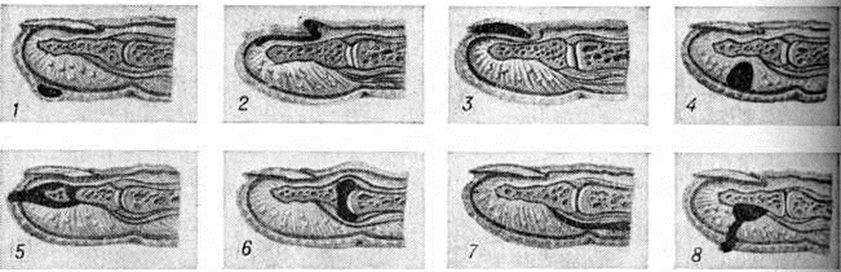

ПанарицийПанариций (латынь panaricium) острое воспаление тканей пальца, возникающее обычно в результате инфицирования мелких его повреждений. Воспалительные процессы, осложняющие обширные ранения пальцев, не относятся к Панариций В этих случали говорят об инфицированных ранах пальцев. Классификация. Для практической работы хирургов наиболее целесообразна классификация Панариций, основанная на учёте анатомической локализации воспалительного процесса (рисунок 1). По этой классификации различают следующие виды Панариций: кожный, околоногтевой (паронихия), подногтевой, подкожный, костный, суставной, сухожильный, пандактилит. Статистика. Чаще Панариций болеют лица, выполняющие работу, связанную с возможностью травмирования рук, загрязнением их смазочными материалами, раздражающими кожу веществами (разнорабочие, грузчики, слесари, трактористы, рабочие ткацкой промышленности и другие). У 80% заболевших наблюдается Панариций ногтевых фаланг I, II или III пальцев правой кисти. Этиология и патогенез. Наиболее распространённым возбудителем Панариций является белый или золотистый гемолитический стафилококк в монокультуре или в ассоциации с другими микробами. Реже воспаление обусловливается кишечной палочкой, протеем, стрептококком и другие. Иногда причиной заболевания служит гнилостная, а также грибковая инфекция. Микробы проникают в ткани из окружающей среды или поверхностных слоёв кожи пальца при мелких, особенно не санированных повреждениях (ссадины, раны, нанесённые острыми предметами иголками, металлическими стружками, деревянными занозами и другие); крайне редко инфицирование происходит гематогенным путём. Возникновению Панариций способствуют снижение иммунологический реактивности организма, истощение, нарушение обмена веществ, эндокринные заболевания, а также длительное воздействие на кожу рук раздражающих веществ, холода, влаги, вибрации, при которых наступают расстройства микроциркуляции и трофики тканей, нарушается защитная функция кожи. Экспериментально доказано, что многие химический вещества и металлы (медь, цинк, кобальт, хром и другие), попадая в рану, оказывают на ткани токсическое действие и также способствуют возникновению Панариций Дальнейшее развитие и особенности течения Панариций в отличие от гнойных заболеваний других локализаций в значительной мере определяются особенностями анатомического строения пальца: обилием на небольшом протяжении функционально важных образований (фиброзные влагалища, сухожилия, синовиальные влагалища, сосуды, элементы, образующие суставы), ячеистостью расположения подкожной клетчатки, пронизанной фиброзными перемычками. Все эти факторы способствуют проникновению инфекции вглубь и переходу её на сухожилия и костносуставной аппарат. Фаза серозного пропитывания тканей обычно короткая, быстро сменяется фазой гнойно-некротического воспаления, так как скопление экссудата в замкнутых пространствах приводит в короткие сроки к нарушению кровообращения, некрозу тканей, гнойному их расплавлению. Клиническая картина. Постоянным признаком всех форм Панариций является сильная боль пульсирующего характера, резче выраженная в центре гнойного очага и при локализации его на ладонной поверхности пальца, где ткани неподатливы и обильно снабжены нервными окончаниями. Боль усиливается при движениях пальца, находящегося обычно в полусогнутом положении. Как правило, имеются выраженные в разной мере припухлость и отёчность пальца, гиперемия кожи, наиболее чётко определяющиеся на тыльной его поверхности, местное повышение температуры. Общие нарушения в организме больных выражены меньше, чем местные. В стадии нагноения боль становится мучительной, приводит к бессоннице; яркая краснота отмечается больше на периферии очага, чем в центре; температура тела повышена (с ремиссиями); определяются увеличение и болезненность регионарных лимфатических, узлов. При кожном Панариций гнойный очаг располагается в толще кожи (рис.< 1, 1) под эпидермисом. Образуется импетигиозный пузырь с серозным, гнойным или геморрагическим содержимым, который может располагаться как на ладонной, так и на тыльной поверхности любой из фаланг, иногда занимая почти всю поверхность пальца. |

Пузырь окружён узким воспалительным валиком. Боль вначале незначительная, но по мере накопления гноя усиливается, становится постоянной, пульсирующей. Иногда очаг гиперемии вокруг пузыря расширяется, присоединяется лимфангиит (смотри полный свод знаний) и регионарный лимфаденит (смотри полный свод знаний), сопровождающийся повышением температуры тела до высоких цифр. Ранее подобное поражение называли лимфатическим панарицием. В современной хирургической литературе этот термин практически не употребляется. При кожном Панариций гнойный очаг в толще кожи может сообщаться с очагом в подкожной клетчатке — так называемый панариций в форме запонки (рисунок 1, 8).

При околоногтевом Панариций— паронихии (смотри полный свод знаний) гнойное воспаление локализуется в толще валика ногтя: в боковом его участке, над корнем ногтя, или на всем протяжении валика (рисунок 1, 2). Кожа валика краснеет, припухает (цветной рисунок 1), из-под валика при надавливании появляются капли гноя.

Подногтевой Панариций характеризуется скоплением гноя под телом ногтя (рисунок 1,5). Он возникает при инфицировании проникающих под ноготь колотых ран, нагноении подногтевых гематом или как осложнение паронихии; протекает остро. Ноготь приподнят, сквозь него просвечивает гной. Ограничение гнойного очага плотной ногтевой пластинкой обусловливает постоянную резко выраженную пульсирующую боль.

Подкожный Панариций— воспаление подкожной клетчатки пальца (рисунок 1, 4) — наиболее распространённая форма Панариций Чаще встречается подкожный Панариций ладонной поверхности дистальных фаланг. Так как на тыльной поверхности пальцев кожа подвижная, а подкожная клетчатка рыхлая и содержит много лимфатических, сосудов, широко анастомозирующих с лимфатических, сосудами ладонной поверхности, то при расположении гнойного очага на ладонной поверхности пальца отёк, припухлость и гиперемия кожи более чётко выражены на боковых поверхностях и тыле пальца. Палец (или фаланга) увеличивается в объёме, становится напряжённым (цветной рисунок 2, 3). Большая толщина, плотность и неподатливость кожи ладонной поверхности, ячеистое расположение подкожной клетчатки способствуют быстрому распространению воспалительного процесса в сторону надкостницы и сухожилий. Боль постоянная, усиливается при разгибании и ослабевает при умеренном сгибании пальца. Точка наибольшей болезненности соответствует локализации центра гнойного очага. Часто больной лишается сна из-за боли, изнурён, температура тела повышается до 38—39°. В гнойное воспаление могут вовлекаться кость, сухожилия, суставы (рисунок 2). Из очага, локализующегося в проксимальной фаланге пальца, гнойный процесс может перейти по рыхлой клетчатке межпальцевых промежутков в каналы червеобразных мышц, дистальный отдел ладони и на проксимальные фаланги соседних пальцев (рисунок 3).

Костным Панариций называется гнойное воспаление пальца с вовлечением в процесс костной ткани (рисунок 1, 5). Различают костный Панариций дистальной, средней и проксимальной фаланг. Костный Панариций может быть первичным, возникающим в результате глубоких колотых ран и заноса инфекции в кость ранящим предметом. Эта форма встречается редко. Преобладает вторичный костный Панариций, причина которого — переход воспаления с мягких тканей на кость. Некроз и гнойное расплавление обусловливают возникновение дефекта кости или образование секвестров. Клинические, картина костного Панариций в ранней стадии не отличается от таковой при подкожном Панариций Вскоре все симптомы становятся резко выраженными. При поражении дистальной фаланги палец приобретает колбообразную форму с напряжённой, блестящей, гладкой кожей. Боль носит постоянный характер. Появляется озноб, головная боль, температура повышается до 39° и выше. В гнойный процесс могут вовлекаться сухожилия, суставы.

Суставной Панариций характеризуется гнойным воспалением межфаланговых или пястно-фаланговых суставов (рисунок 1, 6). Различают две стадии течения суставного Панариций В I стадии в процесс вовлекаются только мягкие ткани сустава: появляется гиперемия кожи, отёк, сглаженность межфаланговых складок; палец приобретает веретенообразную форму. Толчкообразное давление по продольной оси пальца резко усиливает постоянную боль. При пункции сустава (смотри полный свод знаний: Суставы) можно получить мутную жидкость. Во II стадии разрушаются суставные хрящи, боковые связки, наступает деструкция костей, образующих сустав. Возникает патологический подвижность, вплоть до подвывиха в суставе, определяется крепитация суставных поверхностей. Может произойти самопроизвольное вскрытие такого Панариций, при этом образуется свищ с грануляциями и гнойным отделяемым.

Сухожильный Панариций— гнойное воспаление влагалища сухожилия и сухожилия пальца (рисунок 1, 7). Воспаления сухожилий разгибателей пальцев, как правило, не бывает. Сухожилия сгибателей пальцев обычно вовлекаются в процесс вторично, воспаление переходит на них с влагалища сухожилий. Сдавление тонких сосудов, подходящих к сухожилию через мезотендиний, быстро накапливающимся во влагалище сухожилия экссудатом и тромбоз их приводят в короткие сроки к некрозу сухожилия. Гной из влагалища может прорваться наружу с образованием свища (рисунок 4). При сухожильном панариции I пальца гной может распространяться по влагалищу сухожилия длинного сгибателя большого пальца кисти в общее синовиальное влагалище сгибателей и к V пальцу. Возникает так называемый перекрёстный панариций. Возможно распространение гнойного процесса и в обратном направлении — от V пальца к I. Иногда процесс может перейти на глубокие слои предплечья — в так называемый пространство Пирогова—Парона. Этого не наблюдается при сухожильном панариции II, III и IV пальцев, влагалища сухожилий которых изолированы от общего синовиального влагалища сгибателей кисти. Основной признак сухожильного Панариций—постоянная боль по ходу сухожилия, усиливающаяся при попытке разгибания пальца. Несвоевременное хирургическое вмешательство влечёт за собой некроз сухожилия на большом протяжении, отторжение которого происходит очень медленно. Нежизнеспособное сухожилие выглядит серым, тусклым. Сгибательная функция пальца выпадает.

Пандактилит (греческий pan всё + daktylos палец + -itis) — прогрессирующее гнойное воспаление всех тканей пальца, в том числе связок, сухожилий, костей и суставов. Возникает в результате осложнения или неправильного лечения более лёгких форм Панариций Палец резко деформируется, увеличивается в объёме, кожа приобретает багрово-цианотичный оттенок, напряжена, блестит. Имеются свищи, из которых выделяется гной, отторгаются участки некротизированной жировой клетчатки, сухожилий, костные секвестры; нередко наблюдается патологический подвижность и крепитация в межфаланговых суставах.